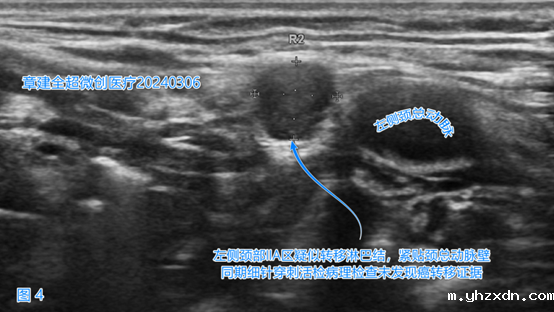

左侧颈部VI(6)区(图4)、

右侧颈部VI(6)、右侧颈部VII(7)区(图5)出现了疑似癌转移的淋巴结。